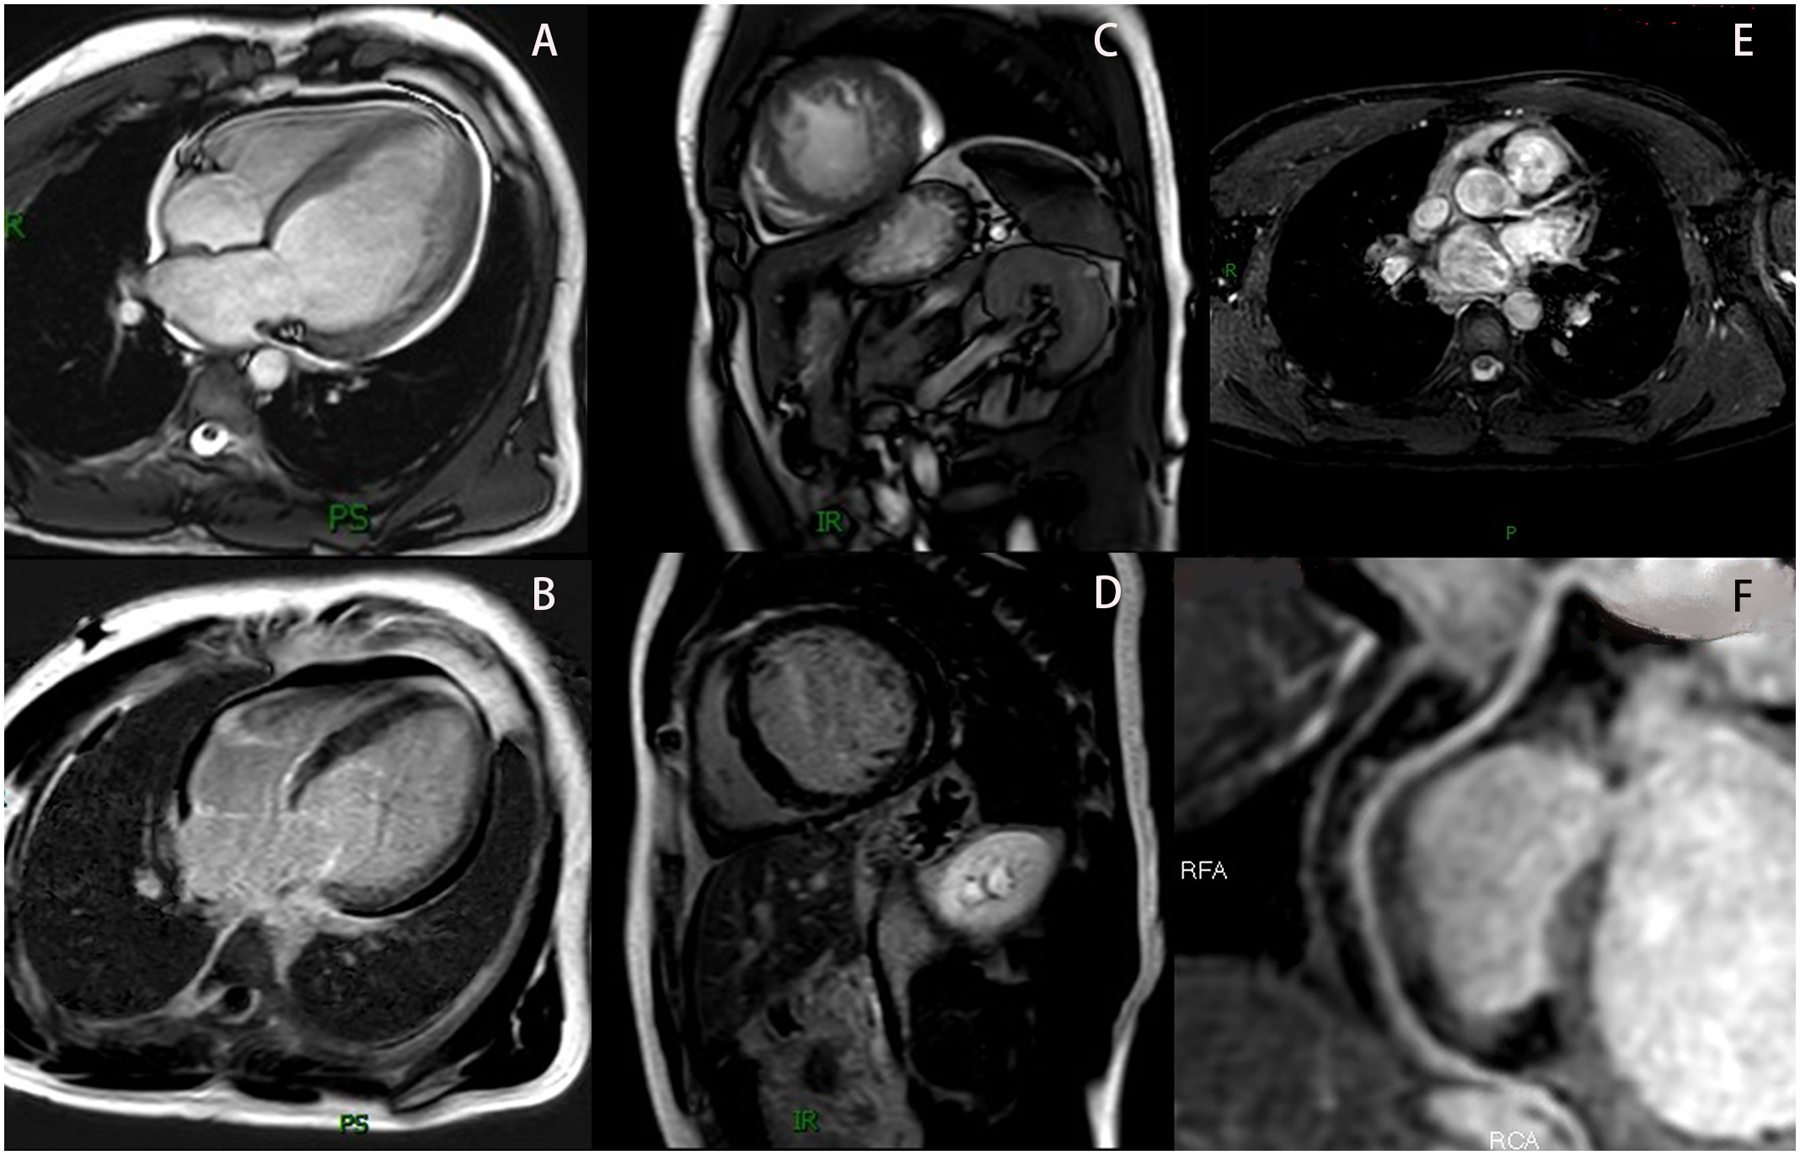

The proband was a 33-year-old man who presented to the outpatient department in May 2022 due to a 12-day history of shortness of breath. He had no history of hypertension, diabetes, hyperlipidemia, or other diseases, and denied smoking, drug use, or alcohol abuse. There was no family history of cardiac disease or sudden cardiac death at a young age. His blood pressure was 125/79 mmHg with a heart rate of 79 bpm. Electrocardiography (EKG) showed sinus rhythm, incomplete left bundle branch block, and left anterior fascicular block. Chest CT scan revealed left ventricular enlargement. Echocardiography demonstrated: left ventricular end-diastolic diameter (LVED) of 68 mm, left atrial diameter (LAD) of 46 mm, right atrial diameter (RAD) of 36 mm, right ventricular end-diastolic diameter (RVD) of 32 mm, interventricular septal thickness at diastole (IVSd) of 9 mm, left ventricular posterior wall dimensions (LVPWd) of 9 mm, and left ventricular ejection fraction (LVEF) of 25% (Figure 1A). The echocardiogram also showed myocardial thinning with non-compacted layer thickening. The patient was diagnosed with heart failure and treated with digoxin, furosemide, spironolactone, and sacubitril/valsartan. After one week without symptom improvement, he was hospitalized.

Figure 1

The patient's echocardiography results. (A) Show the echocardiographic result of the patient's heart at hospitalization (2022). (B) Show the echocardiographic result of the patient's heart at 1 year follow-up (2023). (C) Show the echocardiographic result of the patient's heart at 2 years after discharge, post-infection (2024). (D) Show the echocardiographic result of the patient's heart at 3 years follow-up (2025).

Based on these findings, DCM was diagnosed. Although genetic testing was recommended for further clarification, the patient declined due to financial constraints. After 6 days of treatment with spironolactone, metoprolol, sacubitril/valsartan, and recombinant human brain natriuretic peptide, his condition improved. At discharge, he was prescribed spironolactone, metoprolol, and sacubitril/valsartan. Follow-up showed stable symptoms, and one year later, echocardiography revealed LVED of 60 mm, LAD of 47 mm, and LVEF of 46% (Figure 1B). Vericiguat was added to his medication regimen.

Two years after initial presentation (March 2024), the patient was readmitted for worsening dyspnea following infection. Echocardiography showed: LVED 57 mm, LAD 33 mm, RAD 31 mm, RVD 31 mm, and LVEF 34% (Figure 1C). He responded well to intravenous recombinant human brain natriuretic peptide and was discharged after 4 days. He maintained treatment with spironolactone, metoprolol, sacubitril/valsartan, and vericiguat, with regular follow-up showing stable NYHA class II symptoms, improved dyspnea, and increased exercise tolerance. At the 3-year follow-up, echocardiography demonstrated: LVED 58 mm, LAD 36 mm, RAD 35 mm, RVD 33 mm, and LVEF 40% (Figure 1D). Laboratory tests showed persistent microscopic hematuria (+) without proteinuria and normal renal function (Clinical parameters shows in Table 1).